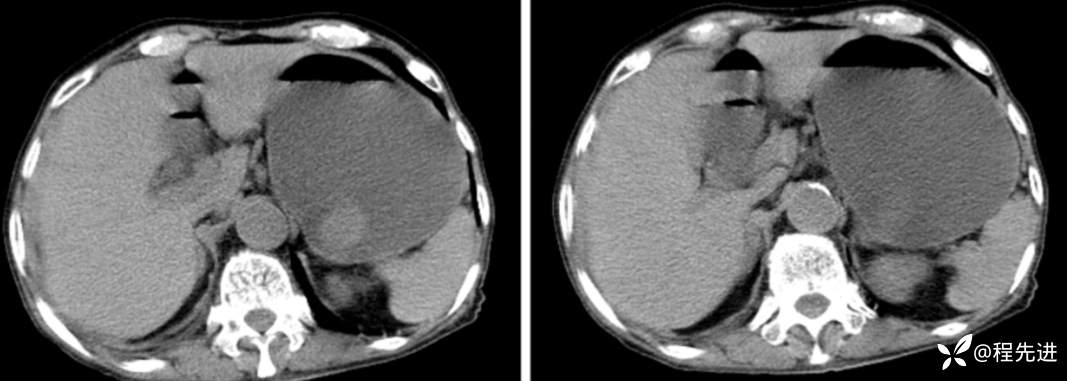

CT

延迟期